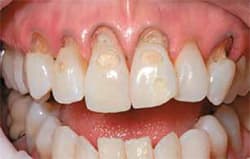

- Severe erosion of the anterior dentition was present upon clinical examination, extending past the enamel into the dentin.

- Direct resin bonding would provide a cost-effective and conservative means of restoring the patient to proper health, function, and aesthetics.

| Note extent of patient’s cavities.(View Figure) | Note extent of patient’s cavities.(View Figure) | ||||||